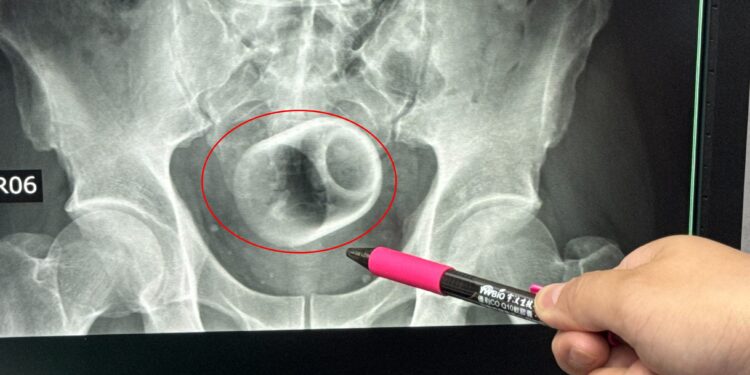

Una radiografía reveló que dentro de él había una taza de cerámica.

Los médicos, que medían unos 6 cm de ancho y 8 cm de alto, intentaron retirar la pieza de vajilla.

Si bien utilizaron instrumentos para intentar sacarlo, la superficie lisa de la copa les dificultaba agarrarla.

Los intentos de utilizar la laparoscopia también fracasaron porque los médicos temían que demasiada fuerza pudiera romper la copa.